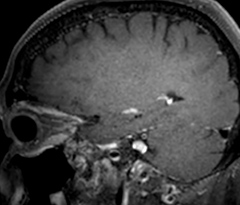

Giant cell arteritis

The 3D TSE T1w black blood MSDE sequence with fat suppression has an isotropic 0.8 mm voxel size and sagittal oblique and axial reformats are made. The images show superficial temporal artery thickening and peri-arterial fat infiltration. The 3D TSE PDw black blood MSDE with fat suppression has 0.55 mm isotropic voxels. The images shows focal involvement of the frontal branch of the superficial temporal artery.

3D TSE T1w BB MSDE

3D TSE PDw BB MSDE